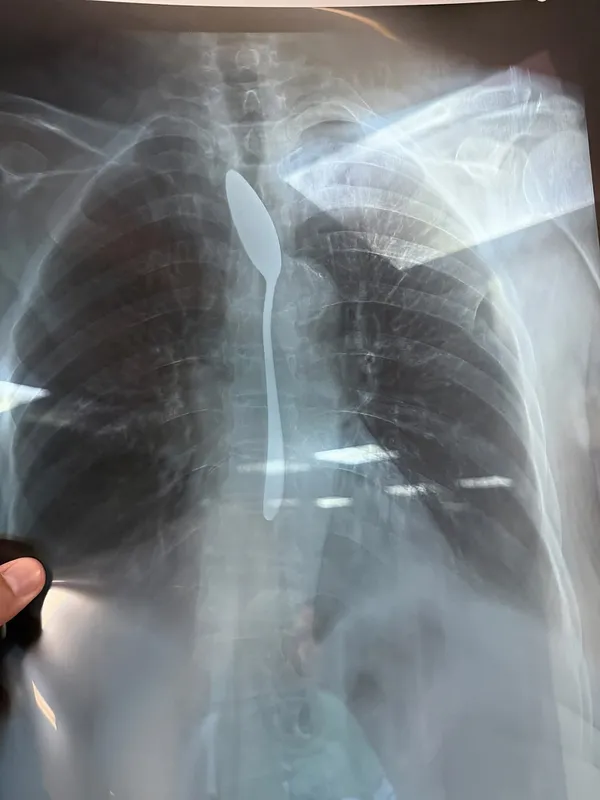

وبعمل الآشعه اللازمه أظهرت صورة واضحة لملعقة شاي كاملة مستقرة داخل المريء، مما استدعى تدخلا عاجلًا لإنقاذ حياتها.

وتم تجهيز المريضة داخل غرفة العمليات واستدعاء الاستشاري المختص، وتم استخراج الملعقة عن طريق منظار المريء في زمن قياسي لم يتجاوز من 5 إلى 7 دقائق، وسط حالة من الترقب داخل غرفة العمليات، وتمت العملية بنجاح كامل دون أي مضاعفات.